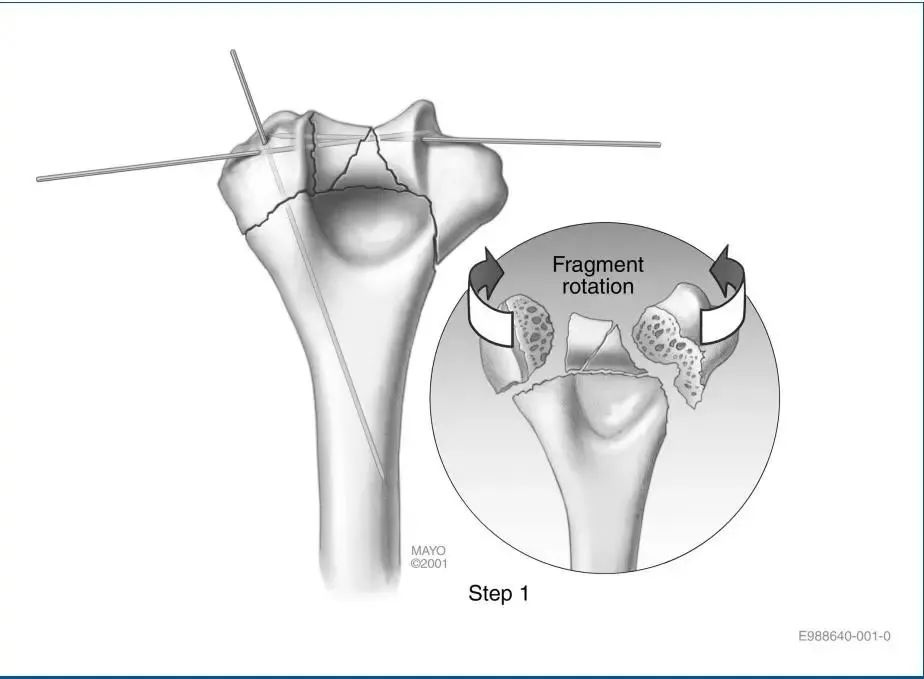

第一步:关节复位术。在轴面上倾向于相互旋转的关节碎片予以解剖复位,并暂时用克氏针固定。重要的是,克氏针应靠近软骨下水平,以避免干扰以后的螺钉放置,并远离钢板放置在外侧柱和内侧柱上的位置。一个或两个适当放置的克氏针可用于暂时固定与骨干对齐的远端骨折。